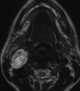

Multiple nerve tumors

A lipoma is a benign tumor made of fat tissue. They are generally soft to the touch, movable, and painless. [Source: Wikipedia ]